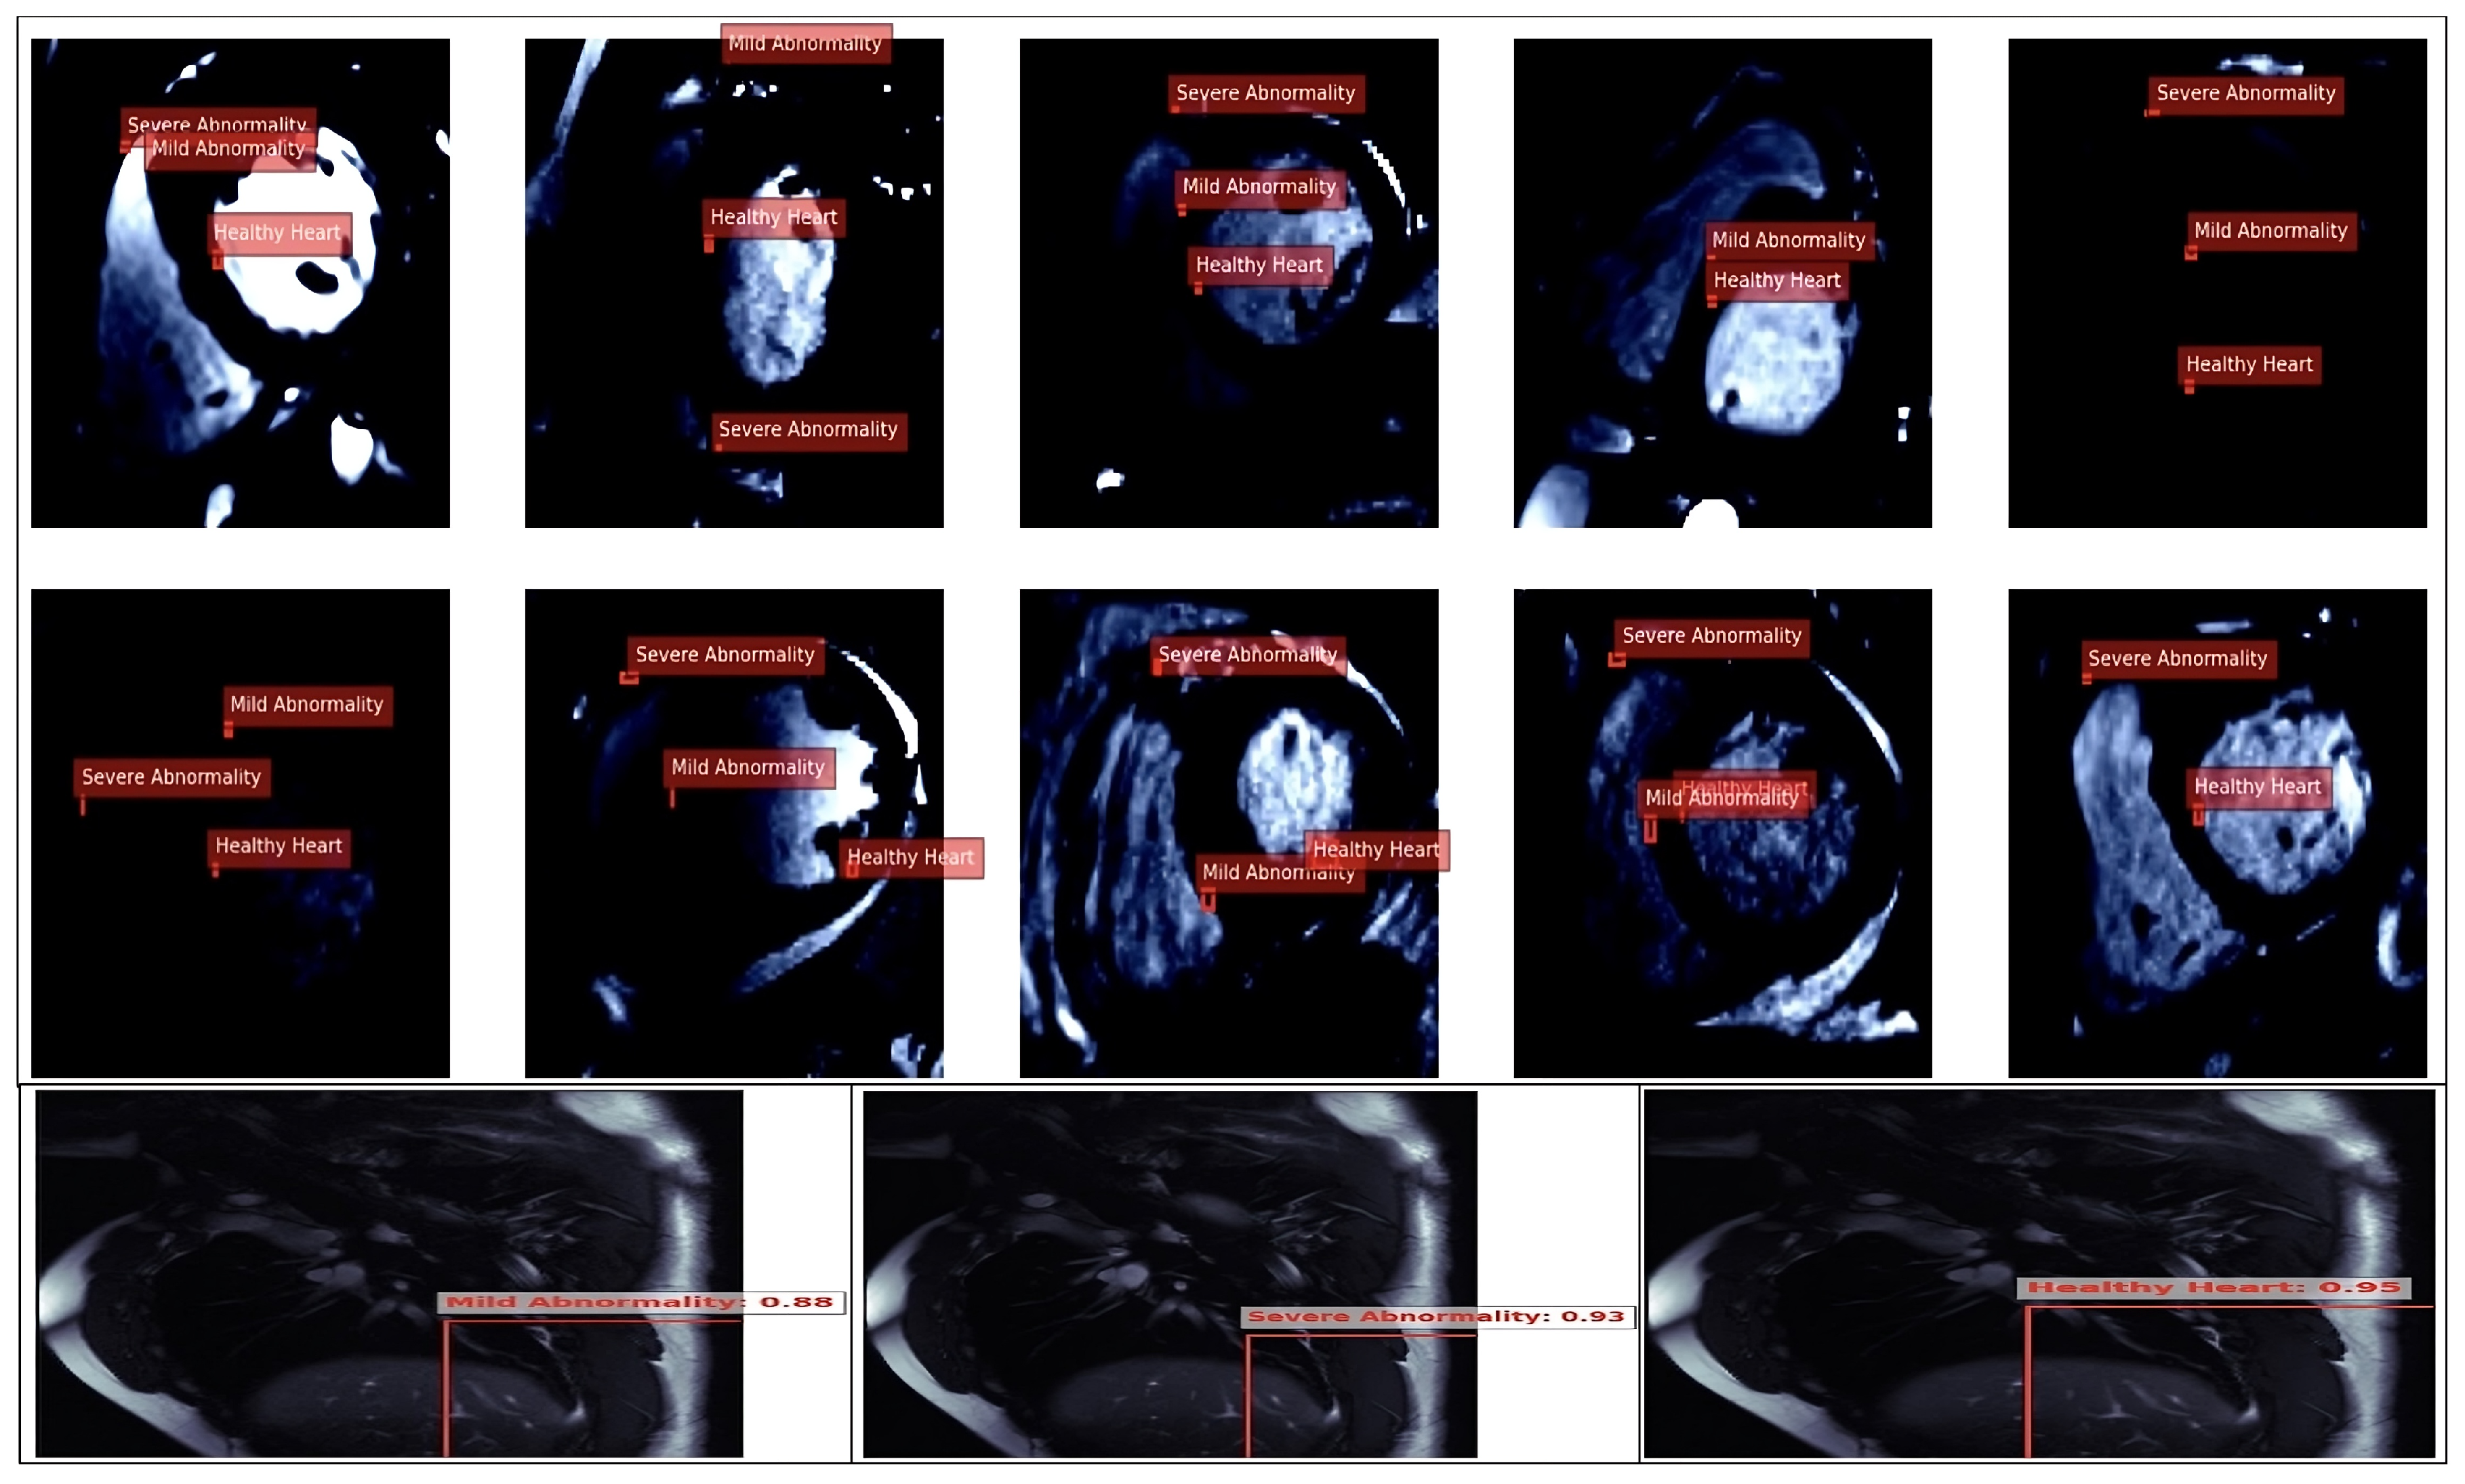

The ResNet model was utilised to classify cardiovascular conditions using an MRI heart imaging dataset. Its robust residual architecture mitigated the vanishing gradient issue and ensured effective deep feature extraction for accurate cardiovascular structure analysis. Heart images highlighting the region in Figure 8.

• Balanced Class Representation:

Classes were evenly distributed across the training ({‘0’, ‘1’, ‘2’}) and validation ({‘0’, ‘1’, ‘2’}) datasets, representing “Healthy Heart”, “Mild Abnormality”, and “Severe Abnormality”. This balanced distribution minimises the risk of skewing model performance towards any single class, thus promoting equitable diagnostics across all conditions.

• High-Quality Annotations:

Precise annotations of the heart region in the MRI images captured relevant anatomical structures, reducing noise and misclassification during training. These high-quality annotations ensured reliable labelling and enhanced the model’s fairness.

• Dataset Size and Diversity:

A total of 400 training and 96 validation images provided a sufficient and diverse dataset to improve the model’s generalisability across varied patient populations. Incorporating various cardiovascular conditions mitigated overfitting to specific patterns or demographics.

• Model Optimisation:

A checkpoint callback was implemented to monitor and preserve the top-performing models based on the minimum validation loss, ensuring unbiased model performance throughout training. Additionally, GPU acceleration and TensorBoard logging facilitated the efficient optimisation and early identification of potential biases in the model’s behaviour.

• Annotation Accuracy and Bias Reduction:

The model demonstrated high annotation accuracy and correlated with low bias tendencies in its predictions. The ResNet model ensured fair and consistent diagnostics, regardless of class representation, by focusing on the relevant cardiovascular features across all classes.

These strategies collectively enhanced the ResNet model’s ability to provide accurate and unbiased cardiovascular health predictions, ensuring its applicability in diverse clinical settings and equitable diagnostics across different patient populations. Additionally, histograms of the widths and heights of bounding boxes in the dataset were constructed, which are visualised in Figure 9. These histograms offered insights into the distribution of the bounding box dimensions across the images, aiding in understanding the diversity and range of features captured by the model during the training set heart image classifications, as shown in Figure 9.

The annotated results demonstrate the model’s ability to classify cardiovascular conditions into “Healthy Heart”, “Mild Abnormality”, and “Severe Abnormality”, with confidence scores of 0.88, 0.93, and 0.95, respectively, indicating high detection accuracy. The confidence distribution across classes reflects balanced detection capabilities, minimising bias toward any specific condition. However, the overlap in classifications (e.g., “Mild Abnormality” and “Severe Abnormality”) highlighted the importance of ensuring robust data diversity to mitigate misclassification risks. These results suggest the model leverages precise cardiovascular feature extraction, enabling fair diagnostics across multiple conditions. The evaluation of the ResNet18 model on the image dataset revealed a sophisticated architecture designed for deep learning tasks. The model comprises convolutional layers, batch normalisation, rectified linear units (ReLU), max-pooling layers, and residual blocks, culminating in an adaptive average pooling layer and a fully connected layer for classification (as shown in Table 5 and Table 6). Using residual connections in the model aided in mitigating the vanishing gradient problem during training, promoting more effective learning of the features relevant to cardiovascular health. The adaptive average pooling layer also helps aggregate features across spatial dimensions, leading to more robust representations for classification tasks.